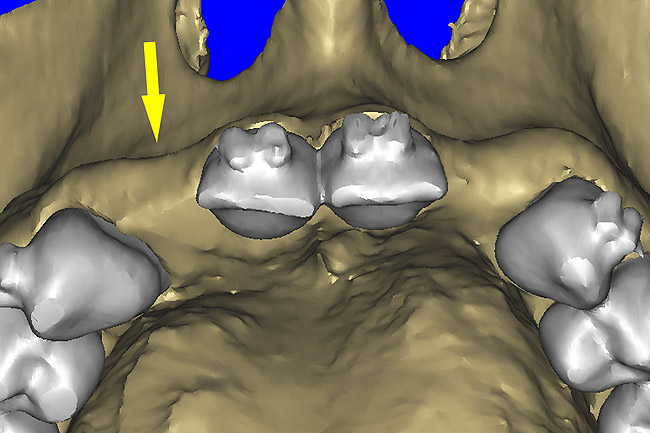

Before the day of surgery, the patient was seen by the orthodontist for the removal of the orthodontic brackets. The patient still was not pleased with the position of the two centrals, and it was determined that this would be addressed after implant placement (Figure 13A). The anatomical variations of the crestal tissue and lack of interdental papilla can be appreciated in the close-up views of the right and left sites (Figure 13B and 13C). There were no surprises on the day of surgery as all of the decisions were made during the planning phase, before the scalpel ever touched the patient. The occlusal view of the CT 3D model revealed the wider alveolar ridge on the right side and thinner crest on the left side (Figure 14A). This was confirmed when the full thickness mucoperiosteal flaps were elevated, and the underyling bone revealed (Figure 14B). The tooth-borne templates were designed to facilitate the drills and drilling sequence specific to the diameters of the predetermined implants (Figure 15A). Each template contained an embedded 5-mm long stainless steel tube, which was approximately 0.2-mm wider than each drill (just wide enough to allow for the drills to rotate freely). Once positioned over the natural teeth, the template was secure and offered precision accuracy in transferring the implant locations from the original software-designed plan, allowing the potential for internal and external irrigation (Figure 15B). The 3.7-mm diameter Tapered Screw-Vent implant drilling sequence requires three drills: pilot, intermediate, and final sizing. Thus, three separate templates were fabricated to a.commodate these sizes. The templates were removed easily and replaced with the next sequential size in less time than it takes to change the drill on the surgical handpiece. After the osteotomies had been.completed, the implants were delivered to the site (Figure 16A and Figure 16B). For this internal hex connection implant, the author r.commends that the flat of the antirotational hex be positioned to the facial for proper orientation of the restorative.components (Figure 17A). Preprepared margins were created from a milled titanium fixture mount transfer post, which was delivered to the implant as support for an immediate transitional restoration. The facial “dot” helped confirm the orientation of the abutment to the facially positioned flat side of the internal hex connection (Figure 17B). Before cementation of the transitional acrylic restorations, a closed-tray, fixture-level impression was made, and a soft-tissue model fabricated.

Figure 14a  The information gained from (A) the 3D model was confirmed when (B) the flaps were elevated.

Figure 14a

Figure 14b  The information gained from (A) the 3D model was confirmed when (B) the flaps were elevated.

Figure 14b